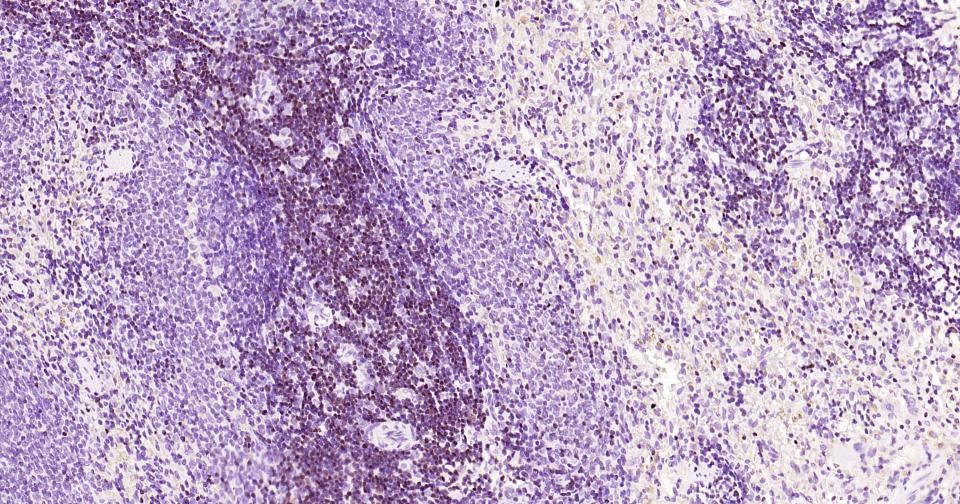

Paraformaldehyde-fixed, paraffin embedded Human Tonsil; Antigen retrieval by boiling in sodium citrate buffer (pH6.0) for 15 min; Antibody incubation with LEF1 Monoclonal Antibody, Unconjugated(bsm-61170R) at 1:200 overnight at 4°C, followed by conjugation to the SP Kit (Rabbit, SP-0023)and DAB (C-0010) staining.